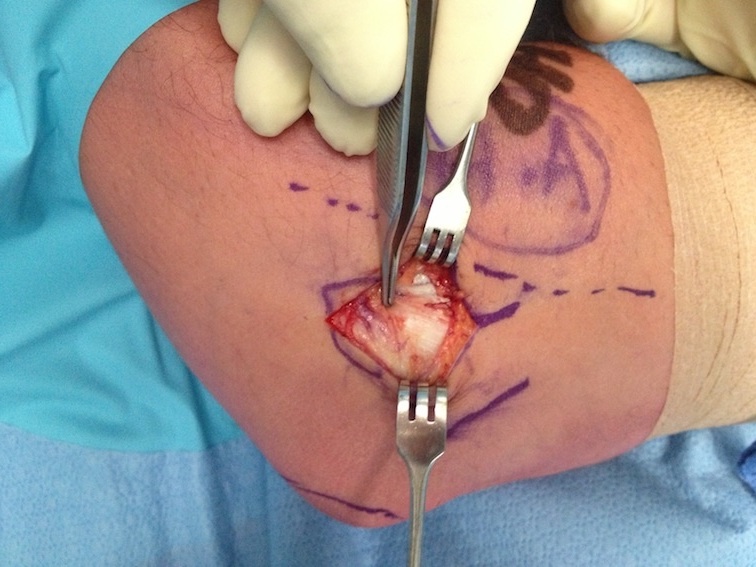

Open tennis elbow release

Technique

Incision centered on common extensor origin

- slightly anterior to radiocapitellar joint

- elevate ECRL (ECRL muscular at this point)

- ECRB is deep and posterior to ECRL

- detach ECRB from lateral epicondyle

- debride degenerative tissue and decorticate underlying common extensor origin

- +/- reattach ECRB with suture anchors

Post tennis elbow repair with anchor